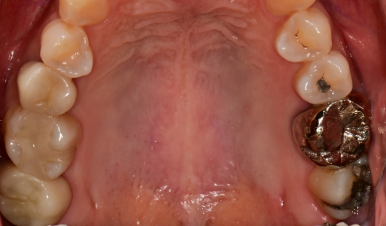

🦷 실제 사례 : 20년 된 금니, 지르코니아로 교체

📌 환자 상황

- 20년 넘게 금니(골드 크라운)를 사용

- 통증 X, 하지만 연식 걱정 + 심미성 개선 원함

정밀 검진 결과,

하악 어금니(#36, #46) 부위에서

보철 경계의 착색과 미세 틈이 관찰되었습니다.